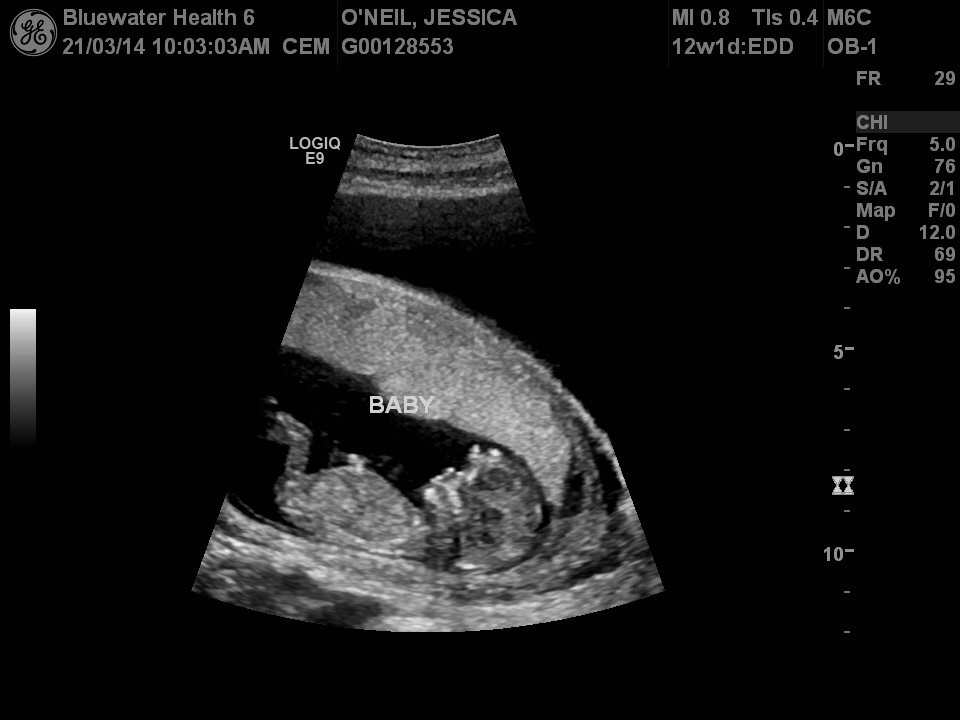

Hey guys! I have attached my 12 week ultrasound pic.......any guesses with the nub or skull theory????Attachment 17777

I think the nub is cut off so I'm not sure:(

I think maybe boy.